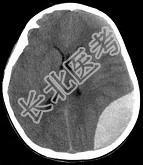

- 单项选择题男性,25岁, 外伤后行CT检查,最可能的诊断为 ( )

A、左顶枕部硬膜下血肿

B、左顶枕部硬膜外血肿

C、左顶枕叶出血

D、脑挫裂伤

E、脑膜瘤